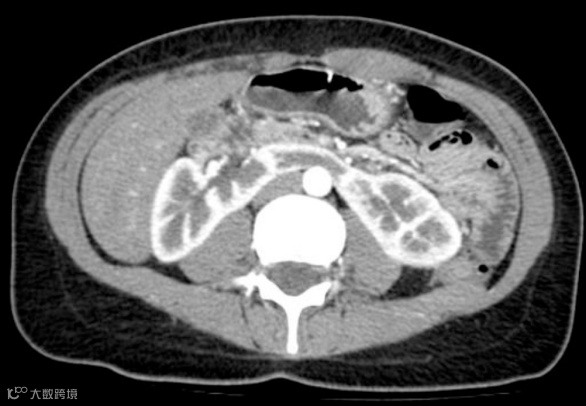

男,55岁,马蹄肾合并双肾多发结石,右肾积水(泌尿系气泡为导尿术后改变)。

CT是发现马蹄肾并发症的最佳工具:

肾积水:由于输尿管在肾盂高位出口或受异常血管压迫所致。

结石形成:尿液引流不畅易并发结石。